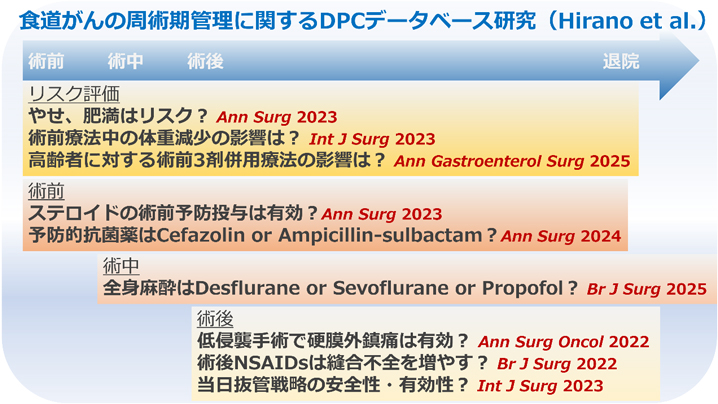

食道がんや胃がんの手術後には肺炎や縫合不全などの合併症をきたすことがあります。合併症が発生すると入院期間が長くなるだけでなく、退院後の回復具合にも影響を与える可能性があります。当院では東京大学・慶應義塾大学・国立がん研究センター中央病院と共同でDPCデータベースという全国規模のビッグデータを用いて、術後合併症のリスクを最小化するための様々な周術期管理(手術前から手術後の治療的サポート)を研究し、その成果を国内学会・メディアのみならず世界のトップジャーナル(米国や英国の一流外科医学雑誌)で発表しています。

当チームの日常診療にもその成果をいち早く導入し、非常に良好な成績を残しています。例えば、当チームで手術された食道がんの患者さまは全国の平均的な施設よりも11日間早く退院(回復)されており、全国でもトップクラスです。